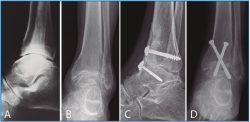

La segunda artrodesis se llevó a cabo durante el año siguiente a la primera intervención. La artrodesis fue tibioastragalina bilateral en 2 pacientes y tibiotalocalcánea (TTC) bilateral en el paciente restante. La estabilización ósea se realizó en un caso con 2 tornillos canulados Acutrak Plus® (Acumed, Hillsboro, EE. UU.) cruzados en ambos tobillos (Figura 1), en otro caso con clavo endomedular retrógrado T2 12 × 200 mm (Stryker, Schönkirchen, Alemania) en ambos tobillos (Figura 2) y en el último caso se utilizaron tornillos canulados Acutrak Plus® cruzados en el tobillo izquierdo y la técnica Putti en el tobillo derecho (Figura 3). La fijación de la artrodesis se realizó con el pie en plantígrado.

Figura 2. Caso 2. Varón de 58 años con artrosis bilateral de tobillo postraumatismo. Radiografía anteroposterior (A) y lateral (B) de tobillo derecho e izquierdo (C-D) preoperatoria. Radiografía anteroposterior y lateral de tobillo que muestra artrodesis tibiocalcánea de tobillo mediante clavo endomedular derecho (E-F) e izquierdo (G-H) a los 3 años de la última intervención (tobillo derecho). En las radiografías (E-H) muestra una consolidación parcial de la artrodesis sobre todo en la parte anterior de la articulación tibioastragalina que no se trató al ser asintomática.